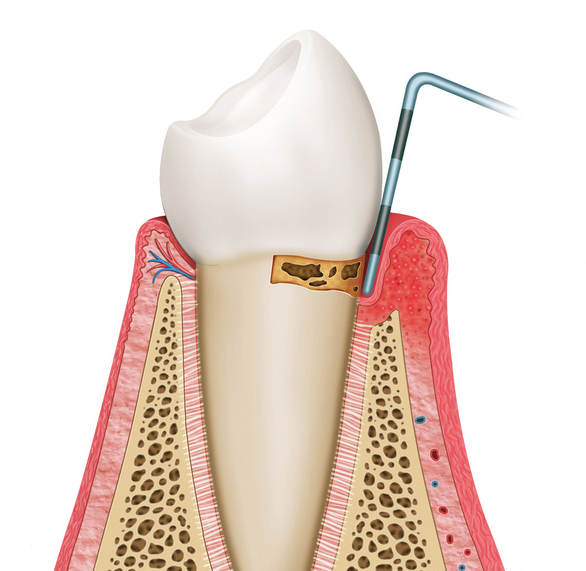

歯肉炎となった後、歯肉炎が進行することにより歯と歯肉の付着レベルが破壊されてしまい、歯周炎となります。

歯周炎が重症化することで歯を支えている歯槽骨の吸収が進行し、その結果、歯の動揺が増大することで最終的には歯の喪失にいたります。

強い口臭と、軽い歯のぐらつきが生じます。

咬めないほど歯がぐらつきます。

歯周ポケットの減少を目的として、切除療法、組織付着法(新付着術、フラップ手術)、再生治療法(歯周組織再生誘導法)などを行います。

歯周組織の健康を維持したり、プラークコントロールを行いやすい口腔環境に改善したりする外科的処置です。形態的、機能的に適切な付着歯肉の幅を形成・維持することを目的としています。